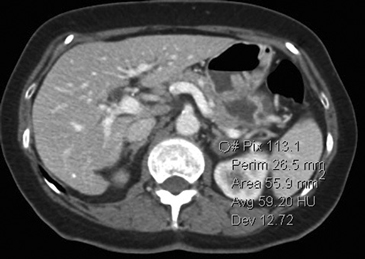

La presencia de lípidos intracelulares disminuye la densidad de la lesión debido a que estos son menos densos que el agua. El primer estudio en reportar la utilidad de la densitometría por TC en la diferenciación de una lesión suprarrenal benigna de una maligna fue el realizado por Lee et al6, utilizando la medición del coeficiente de atenuación o densidad de la lesión expresada en unidades Hounsfield (UH), en una TC no contrastada, demostrando que el coeficiente de atenuación promedio de los adenomas (2,2 UH) fue significativamente menor que la de las lesiones no adenomas (28,9 UH). Utilizando un punto de corte de 0 UH la sensibilidad de la TC no contrastada en la caracterización de un adenoma es cercana a un 47%, con una especificidad de aproximadamente 100% (Figura 9 a y b). Sin embargo, estudios posteriores7 han corroborado que al utilizar un punto de corte de 10 UH, la sensibilidad asciende a un 71%, y la especificidad se mantiene en prácticamente 98%, por lo que este umbral de densidad es el más utilizado en la actualidad. Es importante enfatizar que para una adecuada medición de la densidad, la región de interés (ROI) no debe incluir áreas de necrosis ni de hemorragia, y debe abarcar al menos la mitad o dos tercios de la lesión, para evitar el artefacto por ruido y el efecto de volumen parcial con el tejido adiposo adyacente (Figura 10).

Figura 10. Adenoma suprarrenal derecho. Lesión suprarrenal derecha, cuya densidad es consistente con un adenoma típico. En la imagen se demuestra una adecuada medición de la densidad lesional, con una región de interés (ROI) que abarca al menos dos tercios de ésta.